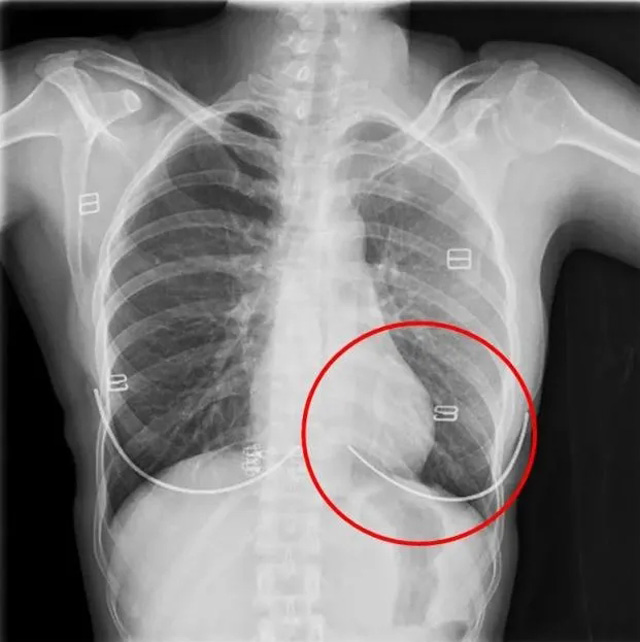

DR是一種比較常規(guī)的基礎(chǔ)影像學檢查方式,適用于人體各部位的健康普查及疾病檢查等優(yōu)勢,在臨床基礎(chǔ)檢查中備受醫(yī)生和患者的青睞。DR體檢車在健康體檢中有著非常重要的地位,由通過電纜串接在一起的探測板、掃描控制器、系統(tǒng)控制及影像顯示器等構(gòu)成。對比CT檢查而言,DR檢查的價格更低,輻射劑量更小它可以讓疾病預防,微細病變可更好顯示診斷治療提供科學的結(jié)果依據(jù)。很多外傷患者都要做DR檢查,來判斷是否骨折或其他的情況。體檢過程中面對DR體檢車做檢查時候需要準備注意什么呢?很多時候大家都有這樣的疑問,身上攜帶的物品是否會對圖像造成遮擋或給機器帶來干擾?檢查前如何準備才不會影響檢查準確性?